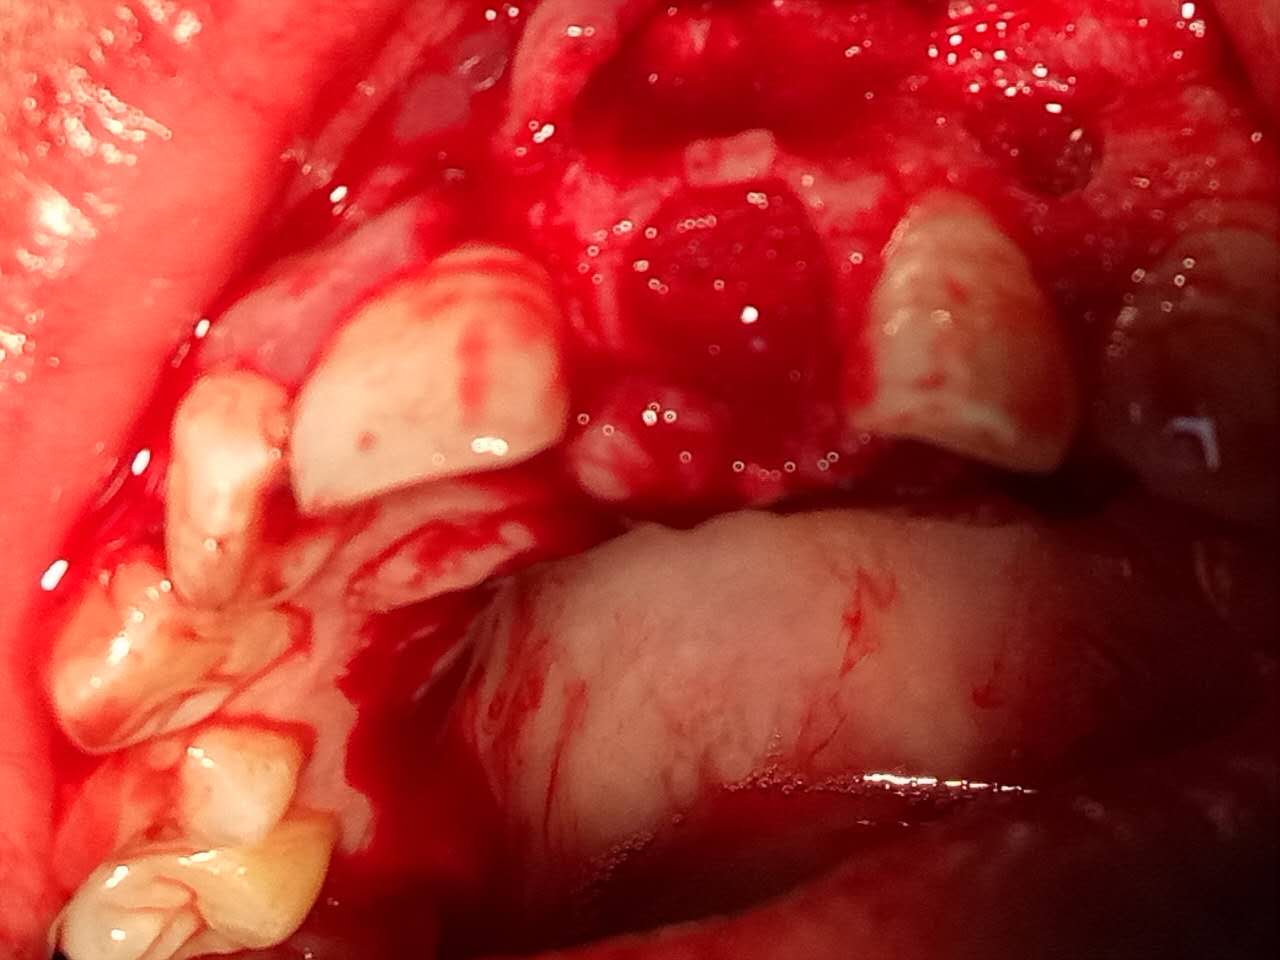

死髓牙2度,沒保留價(jià)值了,外傷造成的外吸收,即使到充也容易出問題。和患者溝通,要求做種植,用了兩個(gè)骨膠原,側(cè)切、尖牙沒事,側(cè)切做了一次根充